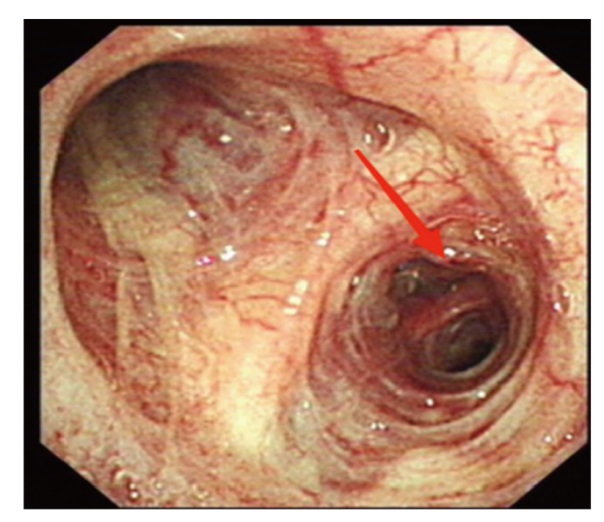

肺癌是我国发病率及死亡率最高的肿瘤性疾病之一,随着低剂量螺旋CT的广泛应用,早期肺癌的检出率逐年升高,双侧同时检出的病例也在逐渐增多,目前对于同期行袖式联合肺叶切除的病例研究较少,现报道1例单孔胸腔镜下左上肺舌段癌袖式切除同期行右肺上叶癌切除术患者的诊疗经过,并复习相关文献,供临床参考。